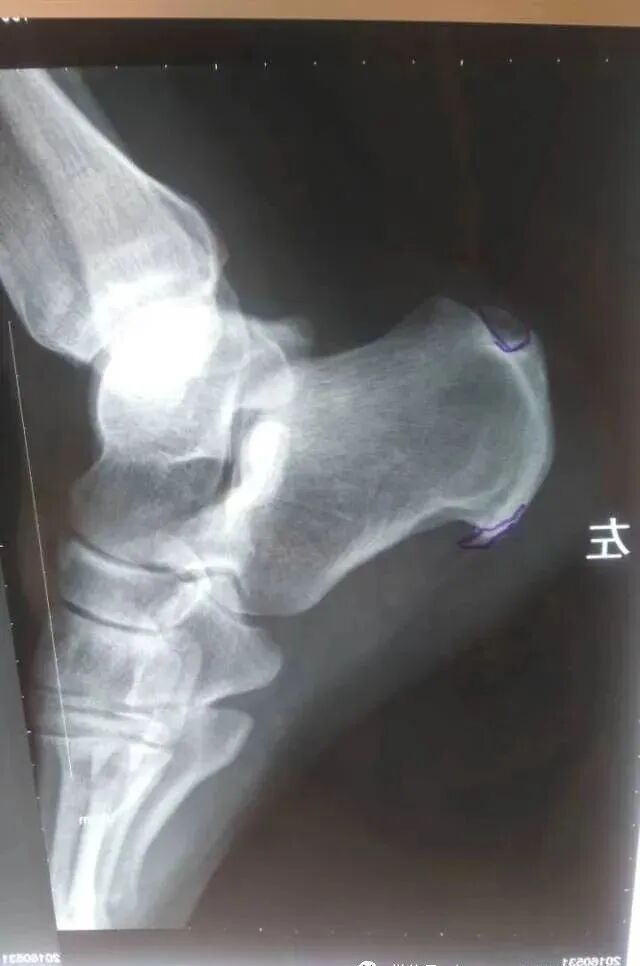

(3)X线示患足跟骨结节处有鸡嘴样骨刺形成。